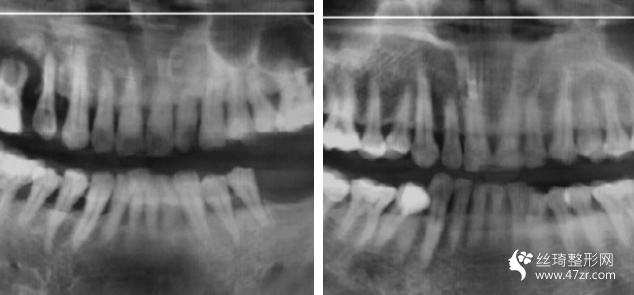

3.長(zhǎng)沙優(yōu)享新天地口腔門(mén)診部張思齊執(zhí)業(yè)醫(yī)師案例展示

這種植牙終于完全好了,特別開(kāi)心,試著吃一些軟食物,我已經(jīng)很久沒(méi)有用左邊咀嚼過(guò)東西了,過(guò)程不疼的!麻藥打好!半個(gè)小時(shí)就好了!今年年頭裝的牙!用到現(xiàn)在了!很牢固!植入種植體,修復(fù)一段時(shí)間就可以戴牙冠了

關(guān)于牙齒的調(diào)節(jié)修復(fù)方案,因?yàn)閭€(gè)人情況各異,并沒(méi)有統(tǒng)一的固定模式,對(duì)于我們自己來(lái)說(shuō)是好的,能夠接受就好,具體的還需要在線咨詢(xún),讓醫(yī)生問(wèn)我們一個(gè)合理的方案。 以后必須學(xué)會(huì)護(hù)理、保護(hù)好我們的牙齒才對(duì),無(wú)論是真牙,還是假牙。